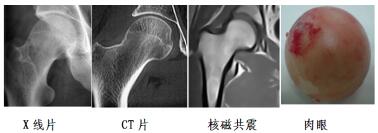

正常股骨頭

壞死股骨頭